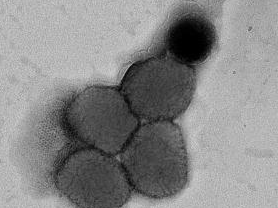

猴痘病毒电镜图截图 图片来源:武汉生物制品研究所

据了解,猴痘是由猴痘病毒感染所致的一种病毒性人兽共患病,临床表现主要为发热、皮疹、淋巴结肿大,其既往主要发生在中非和西非。猴痘已成为当前公共卫生领域最重要的正痘病毒。